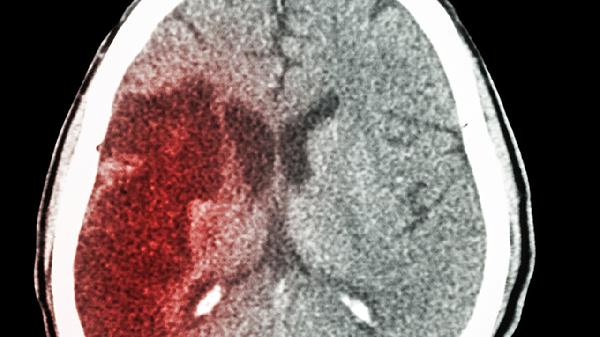

治疗脑梗的中药主要有丹参、川芎、红花、三七、天麻等,需在医生指导下使用。